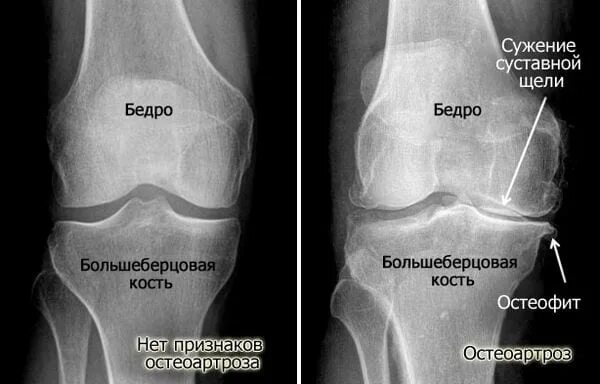

Артроз суставов 1 степени